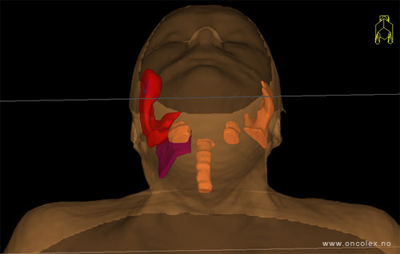

Målvolum

Skisse over hvordan strålefeltet planlegges:

• GTV (Gross Tumor Volume): Identifisert tumor.

• CTV (Clinical Target Volume) GTV + omkringliggende vev hvor det kan væremikroskopisk spredning.

• ITV (Internal Target Volume): CTV + en indre margin som tar hensyn tilindre bevegelser og endringer av CTV.

• PTV (Planning Target Volume): Innstillingsmargin som inneholder ITV og samtidig tar hensyn til antatte pasientbevegelser, samt variasjoner i pasientopplegging og feltinnstillinger.

• Feltgrense. Tegnes som oftest på kroppen.

ICRU (International Commission on Radiation Units and Measurements)